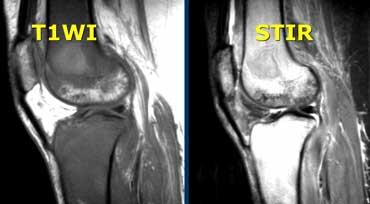

Tủy xương bất thường

Ca lâm sàng bên trái cho thấy tủy xương bất thường.

Trên chuỗi xung T1W, cường độ tín hiệu thấp hơn cơ.

Trên chuỗi xung T2W, tín hiệu rất sáng.

Tín hiệu bất thường lan vào vùng đầu xương.